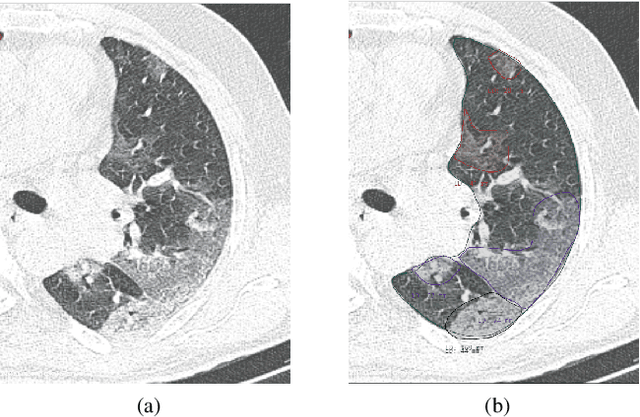

Abstract:Purpose: To present a method that automatically detects and quantifies abnormal tomographic patterns commonly present in COVID-19, namely Ground Glass Opacities (GGO) and consolidations. Given that high opacity abnormalities (i.e., consolidations) were shown to correlate with severe disease, the paper introduces two combined severity measures (Percentage of Opacity, Percentage of High Opacity) and (Lung Severity Score, Lung High Opacity Score). They quantify the extent of overall COVID-19 abnormalities and the presence of high opacity abnormalities, global and lobe-wise, respectively, being computed based on 3D segmentations of lesions, lungs, and lobes. Materials and Methods: The proposed method takes as input a non-contrasted Chest CT and segments the lesions, lungs, and lobes in 3D. It outputs two combined measures of the severity of lung/lobe involvement, quantifying both the extent of COVID-19 abnormalities and presence of high opacities, based on deep learning and deep reinforcement learning. The first measure (POO, POHO) is global, while the second (LSS, LHOS) is lobe-wise. Evaluation is reported on CTs of 100 subjects (50 COVID-19 confirmed and 50 controls) from institutions from Canada, Europe and US. Ground truth is established by manual annotations of lesions, lungs, and lobes. Results: Pearson Correlation Coefficient between method prediction and ground truth is 0.97 (POO), 0.98 (POHO), 0.96 (LSS), 0.96 (LHOS). Automated processing time to compute the severity scores is 10 seconds/case vs 30 mins needed for manual annotations. Conclusion: A new method identifies regions of abnormalities seen in COVID-19 non-contrasted Chest CT and computes (POO, POHO) and (LSS, LHOS) severity scores.